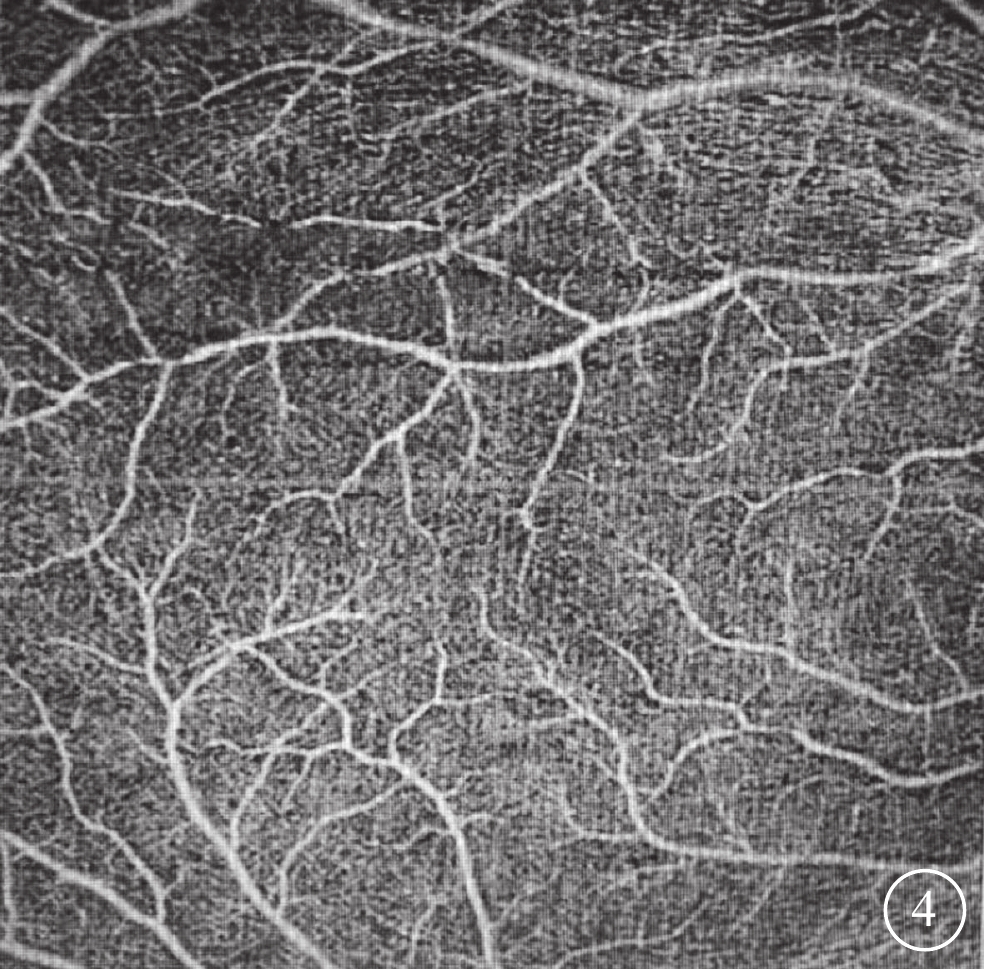

先證者女(Ⅴ11),4歲。雙眼BCVA 0.4。眼前節、色覺檢查未見明顯異常;無眼球震顫。雙眼黃斑中心凹未見反光(圖3A)。OCT檢查,雙眼均無黃斑中心凹,無外核層增寬和光感受器外節段延長,均有內層視網膜在黃斑區域的連續(圖3B)。OCTA檢查,雙眼均未見黃斑中心凹無血管區。先證者母親(Ⅳ14),32歲。雙眼眼前節未見明顯異常。雙眼眼底均未見黃斑中心凹反光。OCTA檢查,雙眼均未見黃斑中心凹無血管區(圖4);OCT檢查,雙眼均未見黃斑中心凹;多焦ERG檢查未見明顯異常;30°視野檢查未見明顯異常。先證者及其母親均診斷為雙眼FVH,Thomas分級均為4級。其余7例(Ⅲ5、Ⅳ1、Ⅳ5、Ⅳ7、Ⅳ16、Ⅴ1、Ⅴ7)中,Ⅲ5、Ⅳ1患者左眼存在黃斑前膜,影響黃斑結構,但視網膜內層在黃斑中心凹處均有連續性,Thomas分級不明確;Ⅲ5右眼、Ⅳ1右眼、Ⅳ5左眼、Ⅳ7左眼、Ⅳ16雙眼、Ⅴ1雙眼、Ⅴ7雙眼均無黃斑中心凹、無光感受器外節段延長,且均有內層視網膜在黃斑區的連續。其中,Ⅲ5右眼、Ⅴ7雙眼有外核層增寬,Thomas分級3級;Ⅳ1右眼、Ⅳ5左眼、Ⅳ7左眼、Ⅳ16雙眼、Ⅴ1雙眼無外核層增寬,Thomas分級4級。